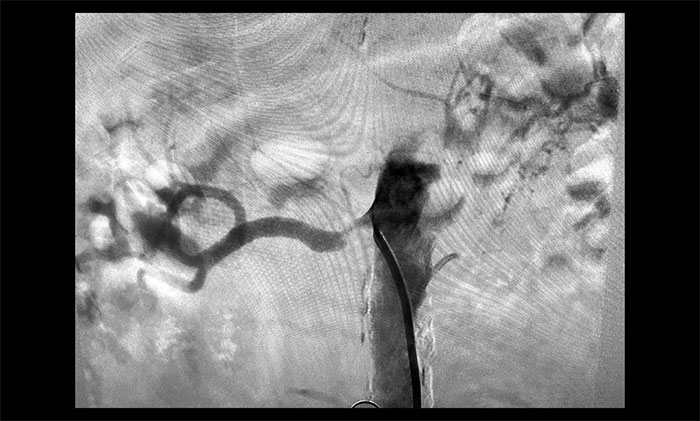

席刚明教授进一步行DSA脑血管造影检查,患者脑动脉多发性狭窄(右侧颈内动脉、大脑中动脉、基底动脉等),左侧颈总动脉闭塞,右侧椎动脉闭塞,右侧肾动脉重度狭窄(狭窄率大于70%),左侧肾动脉闭塞。

▲ 患者右侧肾动脉重度狭窄,左侧闭塞